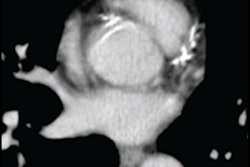

Patients with elevated LDL-C levels but with low coronary artery calcium scores (CAC) on CT angiography may have lower risk of cardiovascular disease than is generally assumed, according to a study published February 11 in JAMA Network Open.

"[Our] findings suggest that atherosclerosis burden, including assessment of CAC, can be used to individualize treatment intensity by identifying patients who are at low risk despite having severely elevated LDL-C levels," the group wrote.

U.S. and European guidelines state that patients with high cholesterol (higher than 190 mg/dl) should be treated with statins to prevent atherosclerotic cardiovascular disease. But some studies have shown that some patients with high cholesterol don't seem to develop CAC, which suggests that treatment for high cholesterol might be better tailored.